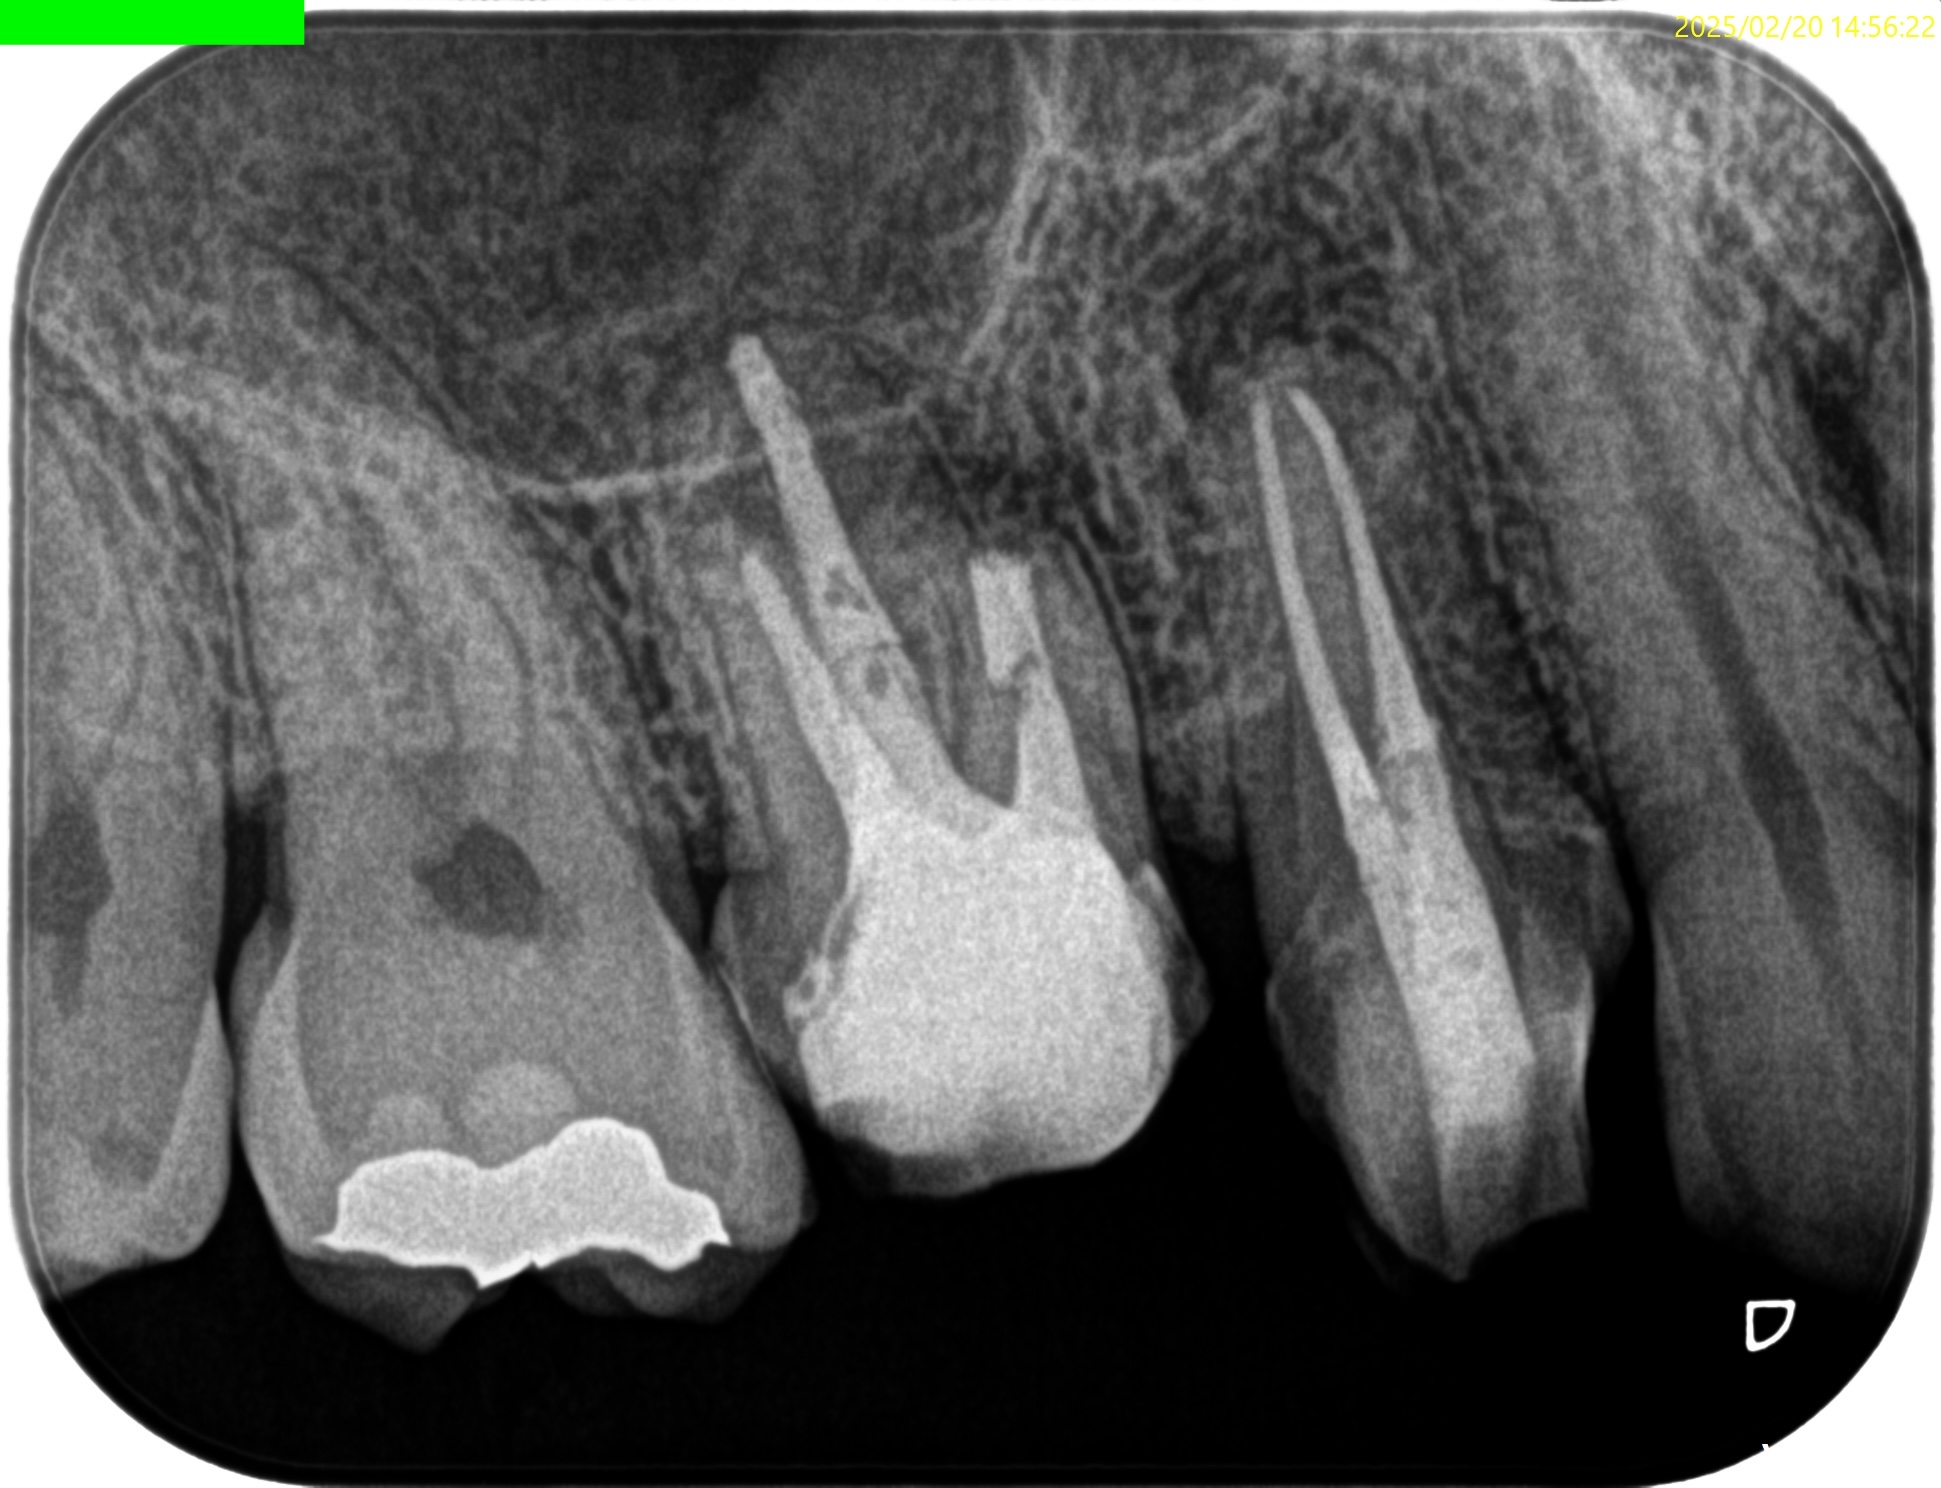

Pre-op Endo test(2025.2.18)

まず、#3 Pのみ再根管治療を行い(2025.2.18)、

この日、#3 MB Apicoectomyを迎えた。

CEJよりも13mm先にApexがある。

が、この際にOsteotomyを行わなくてもApexには辿り着ける。

そしてApexから3mmで切断した時に、頬舌的には4.4mm削るだけで済む。

Very easyな外科治療だ。

そしてその際、Gutta PerchaがMBの中心にあることからこの根管は1根管であるということまでわかる。

まさにSuper easyなApicoectomyである。

充填後、CBCTとPAを撮影した。

問題はないだろう。